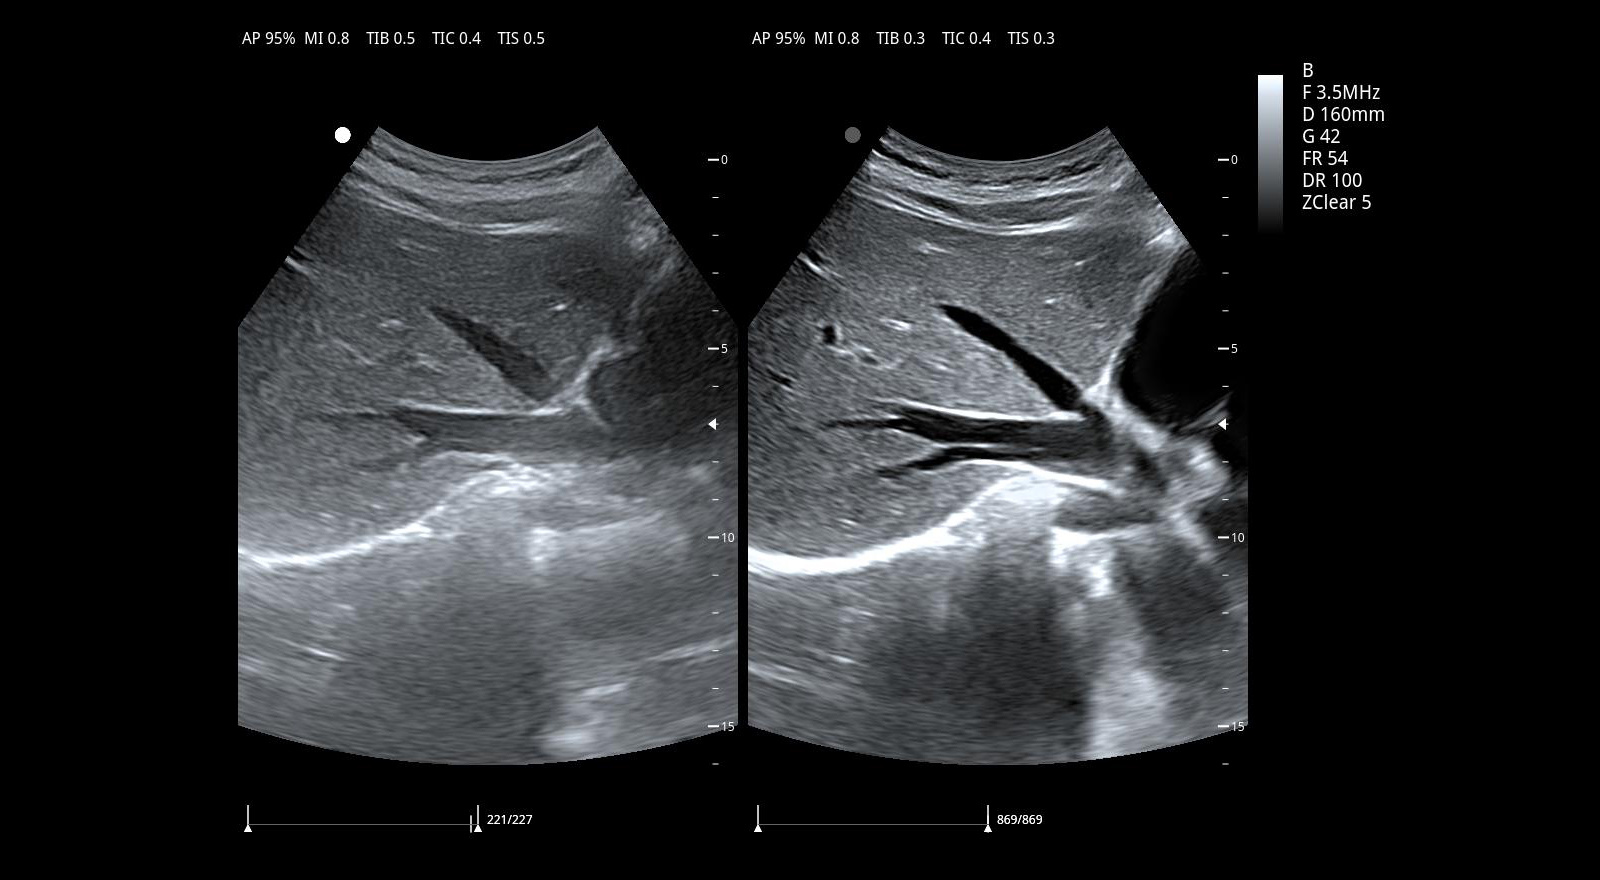

Imágenes clínicas extraordinarias